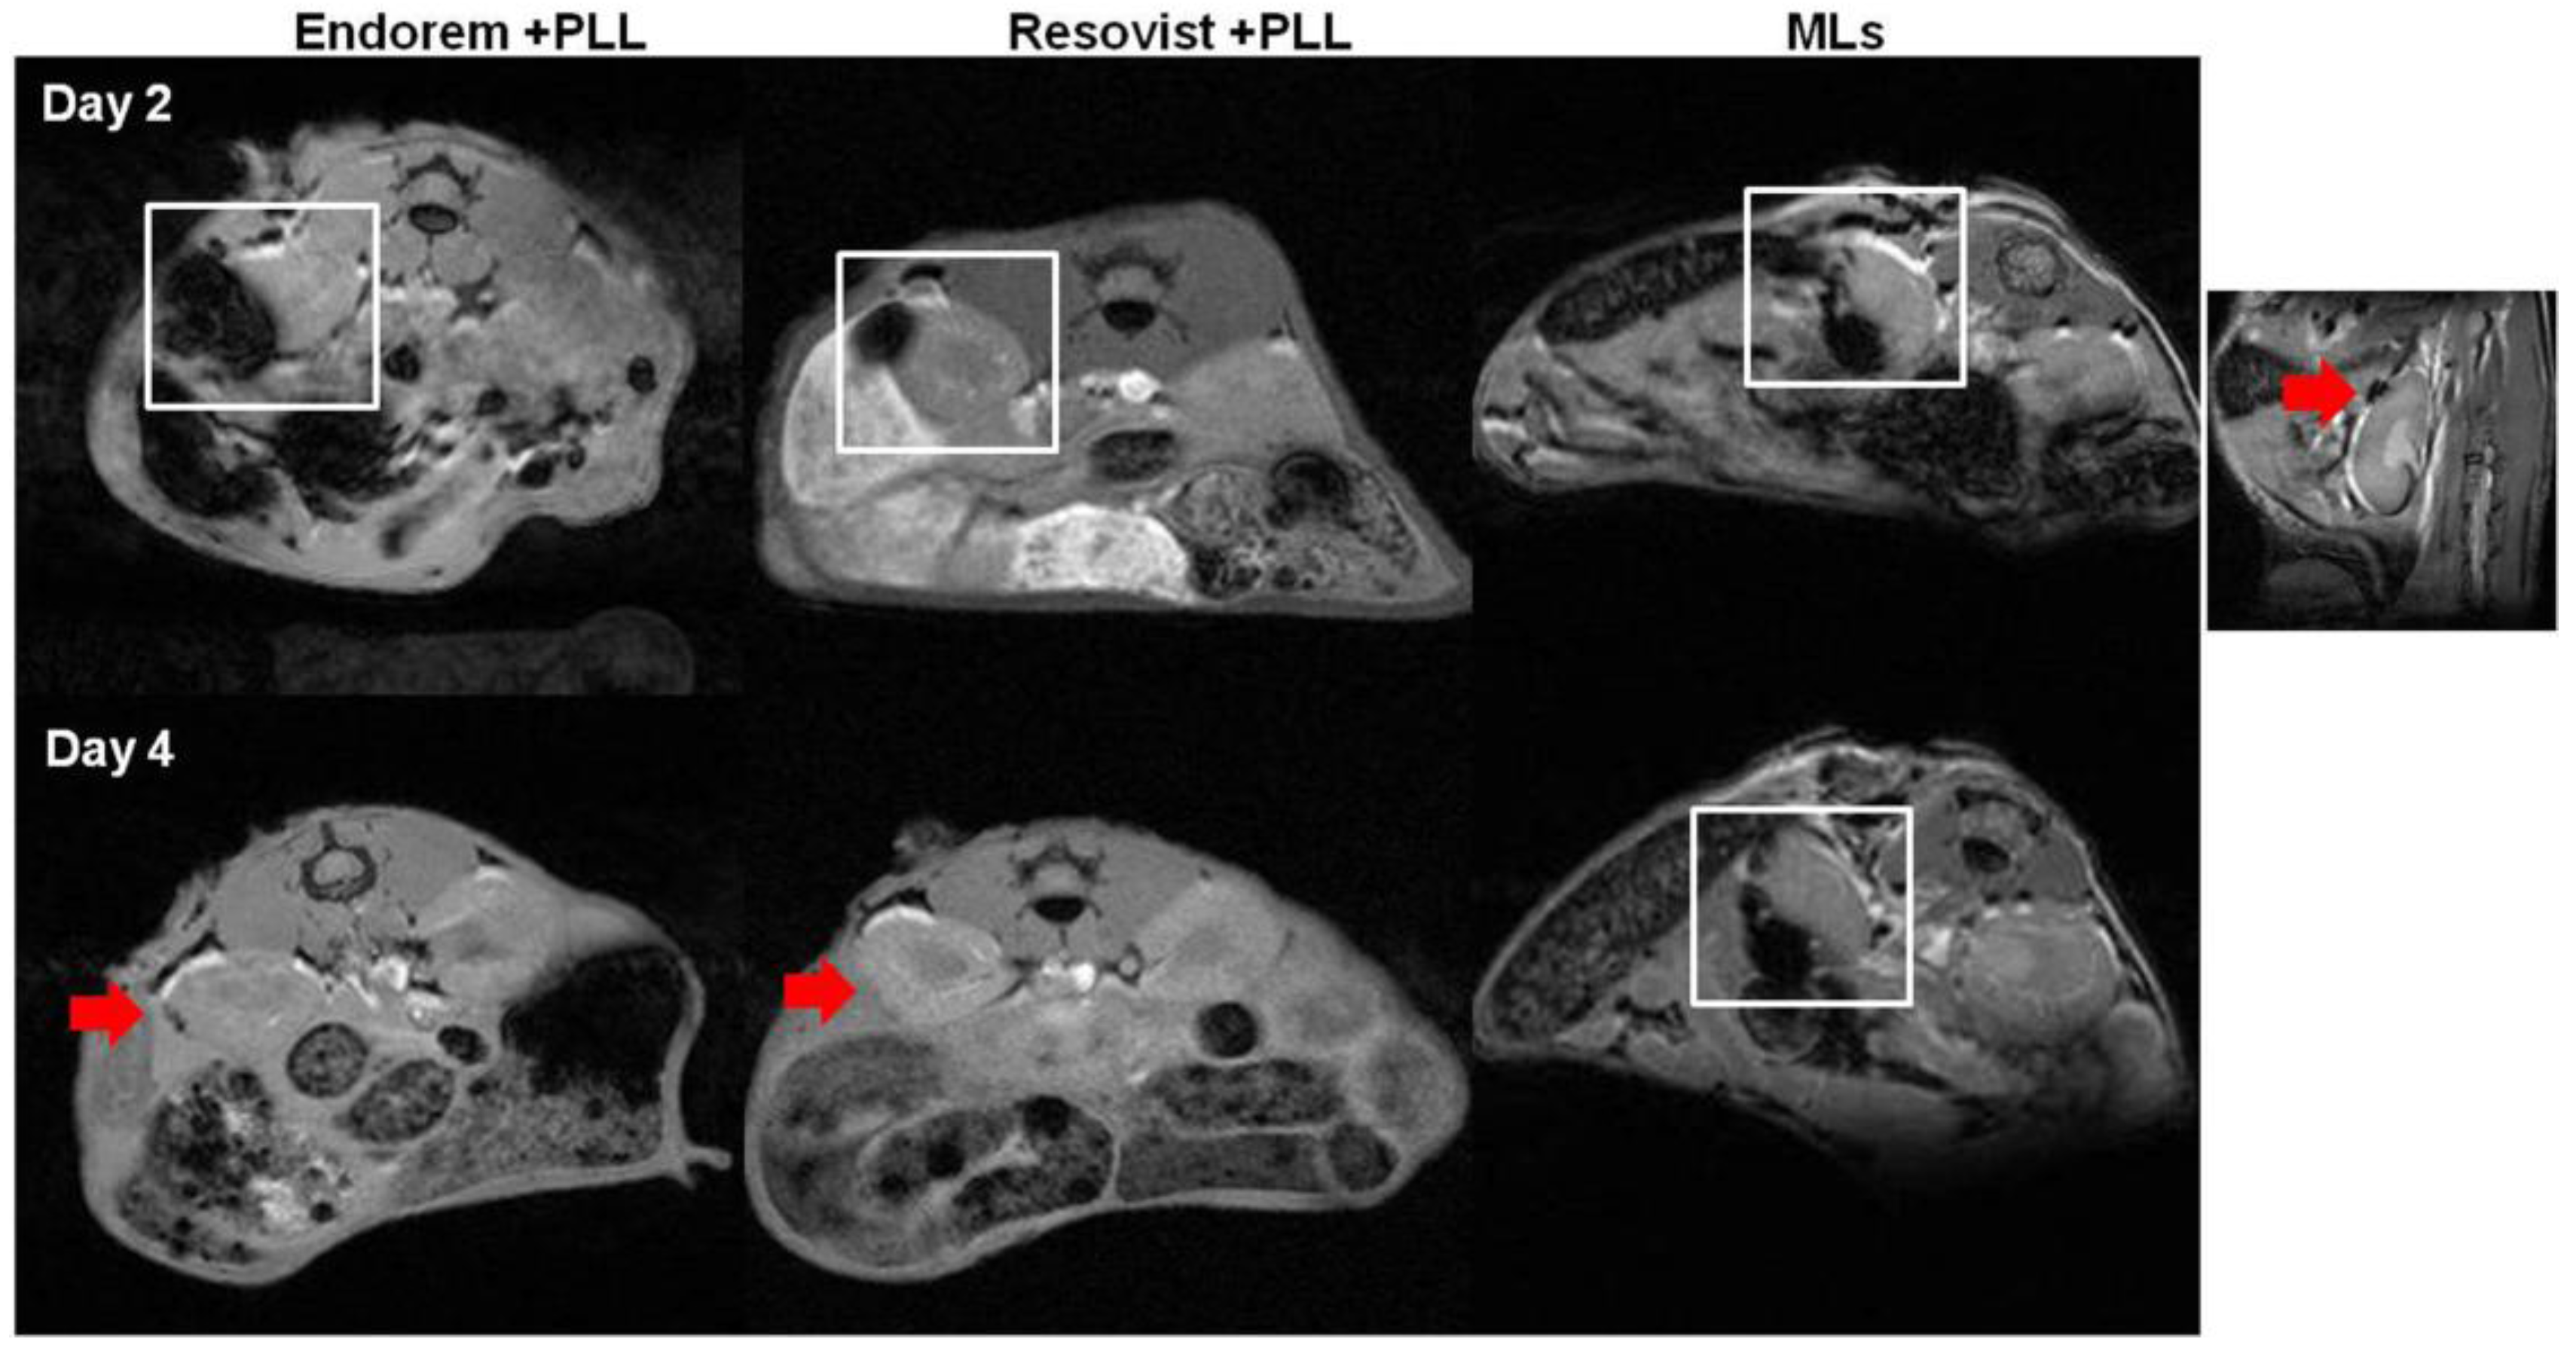

We assessed the feasibility of monitoring islets transplanted in the sub-capsular space of kidneys in healthy mice longitudinally, by using in vivo MR imaging. We implanted 200 PIs, labeled with Endorem (+PLL), Resovist (+PLL), or MLs under the left kidney capsule. Figure 6 indicates MRI performed at the different time points, indicating a marked decrease in the signal intensity (white square in Figure 6) on T2-weighted MR images. PIs labeled with MLs showed a hypointense signal until day four, whereas PIs labeled with Endorem or Resovist (+PLL) did not show any hypointense signals by day four. The higher MRI sensitivity of MLs can be explained by intracellular aggregation caused after partial degradation of the outer lipid layer in the lysosomal environment [31,32].

Figure 6.

MR imaging of transplanted islets: MR imaging was performed to detect the labeled islets in vivo. The hypointense sub-capsular region (highlighted by white square) indicates PIs labeled with Endorem + PLL and Resovist + PLL. Endorem or Resovist + PLL-labeled islets were not detectable on day four in the sub-capsular region (red arrows), whereas PIs labeled with MLs were detectable until day four (indicated by white square). The right corner image indicates a prominent black spot (red arrow) seen on the sub-capsular region after transplantation of PIs labeled with MLs.